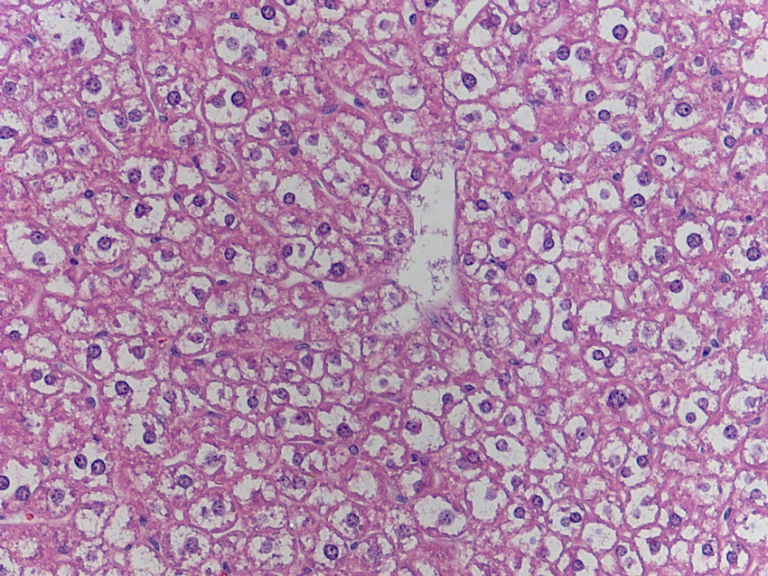

ADIPOSE TISSUE:

Adipose tissue is fat, a connective tissue that insulates and cushions the body.

It is pretty easy to identify, due to the fact that it looks nothing like most other tissue.

Adipose cells found in my slides:

Same slide with lower magnification.